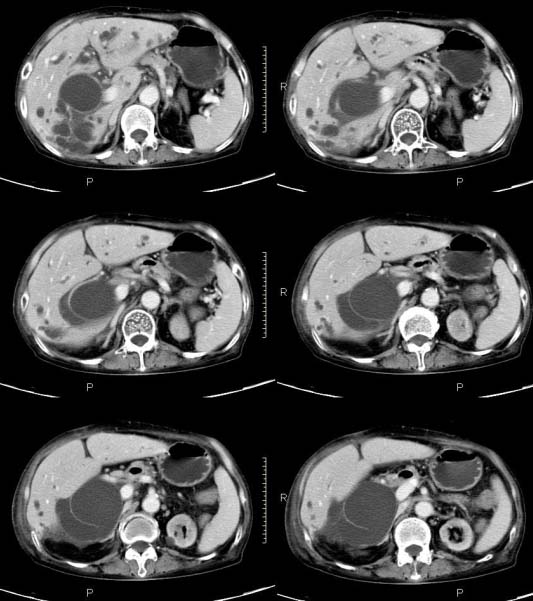

女,71岁,腹痛、腹胀、黄疸20余天,b超示肝内外胆管高度扩张内伴絮状物质(未提示梗阻部位或结石影),经抗炎解痉治疗后,肝功能有所好转,但胆道梗阻状态并未减轻。患者曾于1970年代做过胆囊切除术,1997年因胰腺炎而手术;且患者有糖尿病10余年。ct图片传了静脉期,未传动脉期了,最后一序列为3.2mm薄扫,请各位同仁仔细看看,确定一下胆管梗阻的部位,是炎性梗阻还是肿瘤性梗阻,是否与胰腺炎有关系,扩张胆总管中段前缘是否是胰管。请高手们最好用图示来指出梗阻部位。

扩张的胆管直达胰头,但胰头增大又不明显,且无异常密度影。考虑壶腹部占位。

肝内外胆管显著扩张,考虑先天性胆管囊肿(ⅳ型)。

肝内胆管远侧、近侧不比例扩张,以近侧为明显。胆总管扩张。考虑先天性胆管囊肿(ⅳ型)。